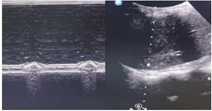

辅助检查:(1)脑脊液检查:生化指标、蛋白均在正常范围内。血清甲状腺功能、肌酶均阴性。(2)痰培养:铜绿假单胞杆菌。G实验、GM实验均阴性。(3)胸部CT:双肺炎症,双肺背侧肺野部分不张并实变(图1)。(4)膈肌功能超声:呼吸末膈肌厚度约1.1 mm,吸气末膈肌厚度约1.4 mm,膈肌增厚度约27%,膈肌移动度10 mm(图2)。(5)支气管镜:右肺中下叶、左肺下叶各级支气管可见大量痰液(图3)。